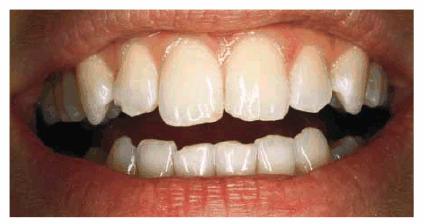

smile (Figur 323s1823d es 18-1A, and 18-1B). Decades ago, the full crown

Figur 323s1823d e 18-1A: This 21-year-old girl had chipped her anterior incisors when she was a teenager.

Figur 323s1823d e 18-1B: Cosmetic contouring was the most conservative treatment available and was performed in a less than 1-hour appointment.